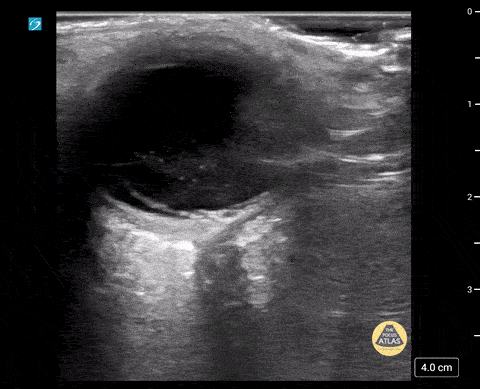

Peds-Orbital - Vitreous Hemorrhage/Macular Detachment

8 yo male was on a scooter and struck his head on handle. He presented to the ed with blurry vision. POCUS shows vitreous hemorrhage with a retinal detachment. Contributor: Richard Ramirez, MD Nicklaus Children's Hospital